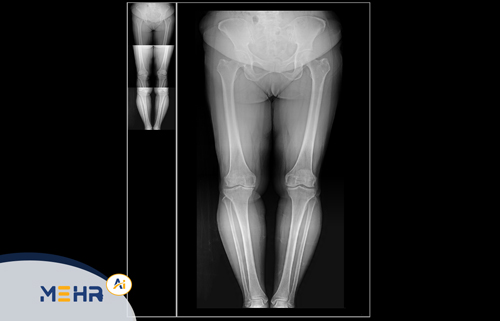

• مشاهده تصاویر MRI در نماهای Axial، Sagittal، Coronal

• ابزارهای پیشرفته برای Zoom، Rotate، Window Level و Distance Measurement

• مقایسه تصاویر چندمرحله‌ای بیماران برای بررسی روند درمان

• بازسازی سه‌بعدی (3D Reconstruction) از داده‌های حجمی MRI

• پشتیبانی از سه‌بعدی‌سازی تصاویر برای تشخیص دقیق‌تر ضایعات